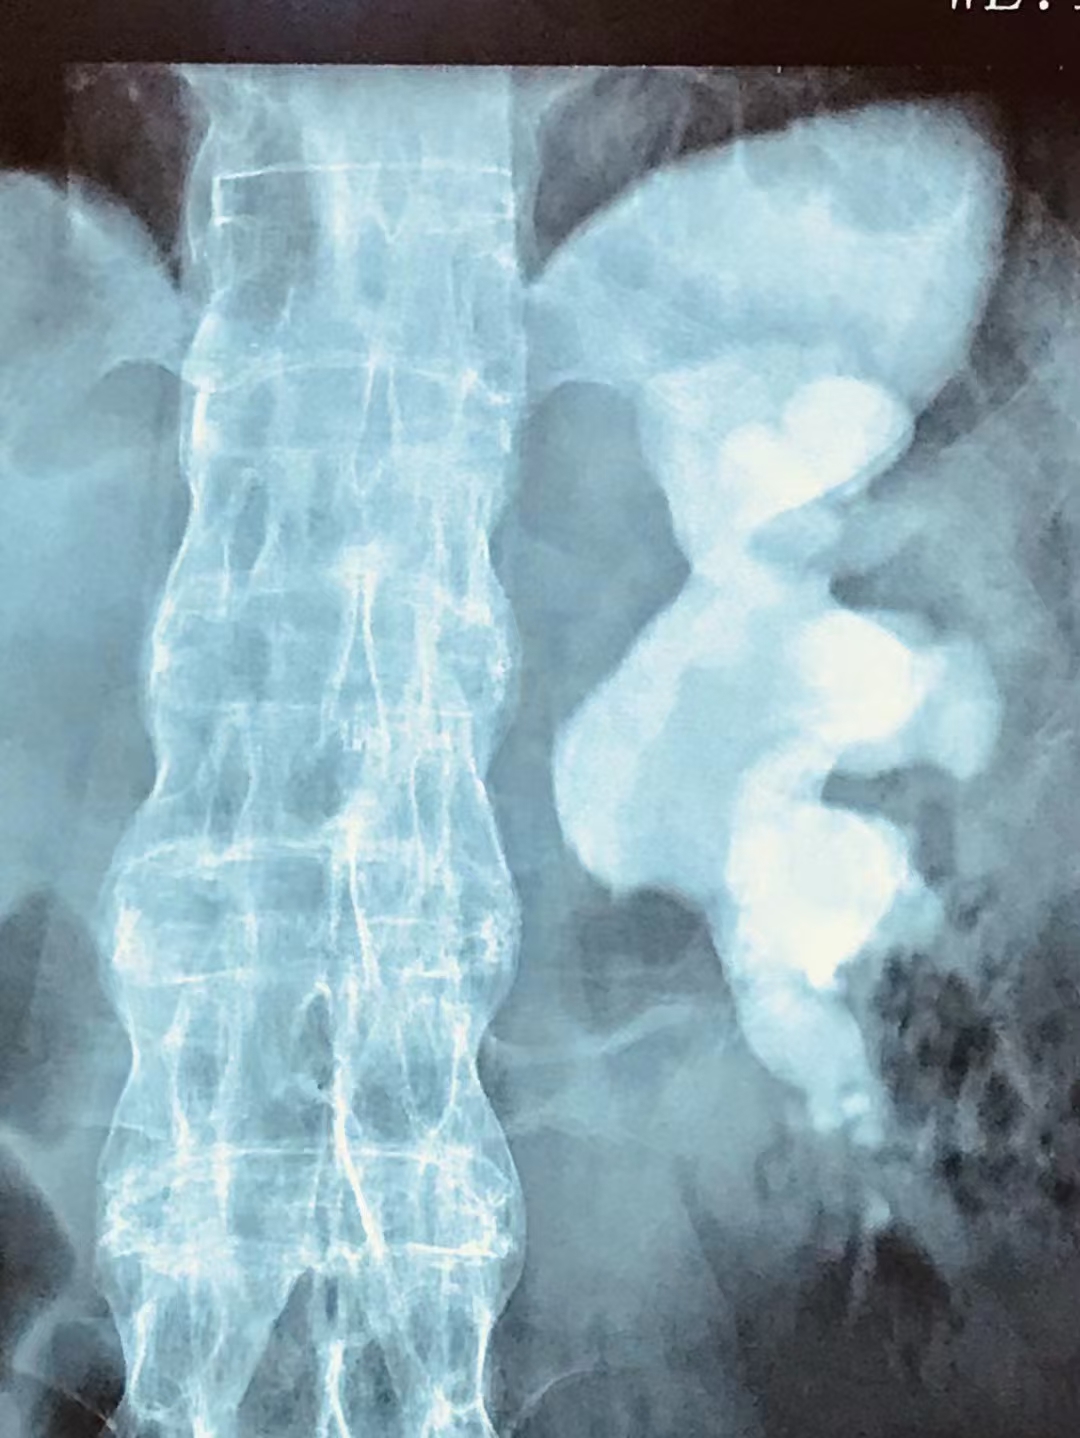

很多有尿路结石困扰的患者,都有过排尿时排出小结石的经历。由于尿路结石可自行排出或经治疗后排出,排出的结石大多小如砂砾,结石排出时可伴有尿路疼痛、血尿或脓尿等。

四川结石病医院泌尿外科常立高主任表示:有时单个的结石排出后,彩超检查发现尿路中没有新的结石影,说明结石已经全部排出或结石呈单个发生。

有时排出结石后经进一步的检查发现尿路中还存在有结石影,表明结石没有排净或结石为多发性,应进行进一步的检查。

图片来源:网络,侵权请联系删除